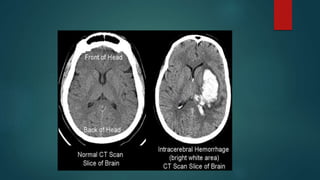

Pathophysiology

 Interruption of blood flow to the part of the brain

 Rupture of blood vessels with bleeding into cerebral parenchyma.

 Interruption of blood flow of arterial or thrombotic d/s- Ischemic stroke.

 Rupture of blood vessels with bleeding into cerebral parenchyma-

Hemorrhagic stroke.